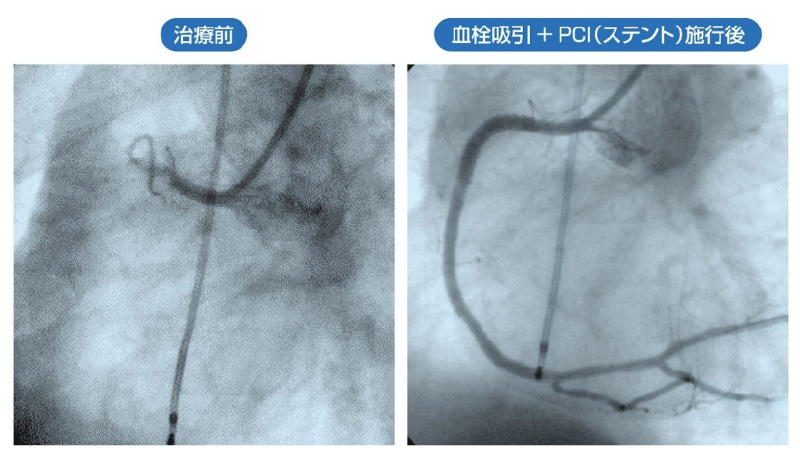

心筋梗塞

症状としては、激しい胸の痛み、重い感じ、呼吸困難、冷汗、嘔気、嘔吐などがあります。狭心症と違い、痛みが通常30分以上続きます。ただし、高齢者や糖尿病患者では胸痛を自覚しないこともあり、なんとなく元気が無い、吐き気などが主な症状であったりすることから、見落とされるケースも少なくないので、要注意です。

出典:インフォームドコンセントのための心臓・血管病アトラス

胸痛発作が始まってから6時間以内に治療を行えば、大部分の心臓の筋肉を救うことができます。血栓を溶かす薬を注射、カテーテルによる適切な治療をすみやかに行うことが現在一般的です。心筋梗塞をおこすと、心臓の筋肉に酸素と栄養が供給されなくなり、その領域の心筋が死んでしまうおそれがあるため、一刻を争う治療が必要です。循環器専門医による詳しい検査を早急に受けることをすすめます。